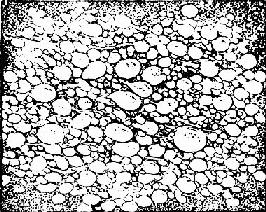

来源于胚胎滋养细胞。由于绒毛水肿增大,形成大小不等的水泡,相连成串,状似葡萄,故称葡萄胎(图167)。

水泡状胎块

图167 水泡状胎块